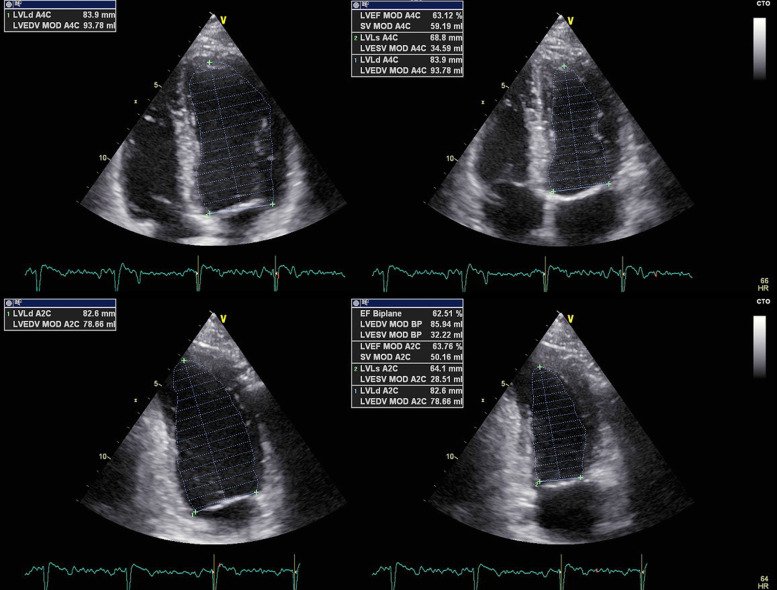

Echo also evaluates overall heart pumping ability.

Using the Simpson biplane method, we calculate left ventricular ejection fraction (LVEF).

Reduced EF in CAD patients often reflects myocardial damage from ischemia or infarction. Image